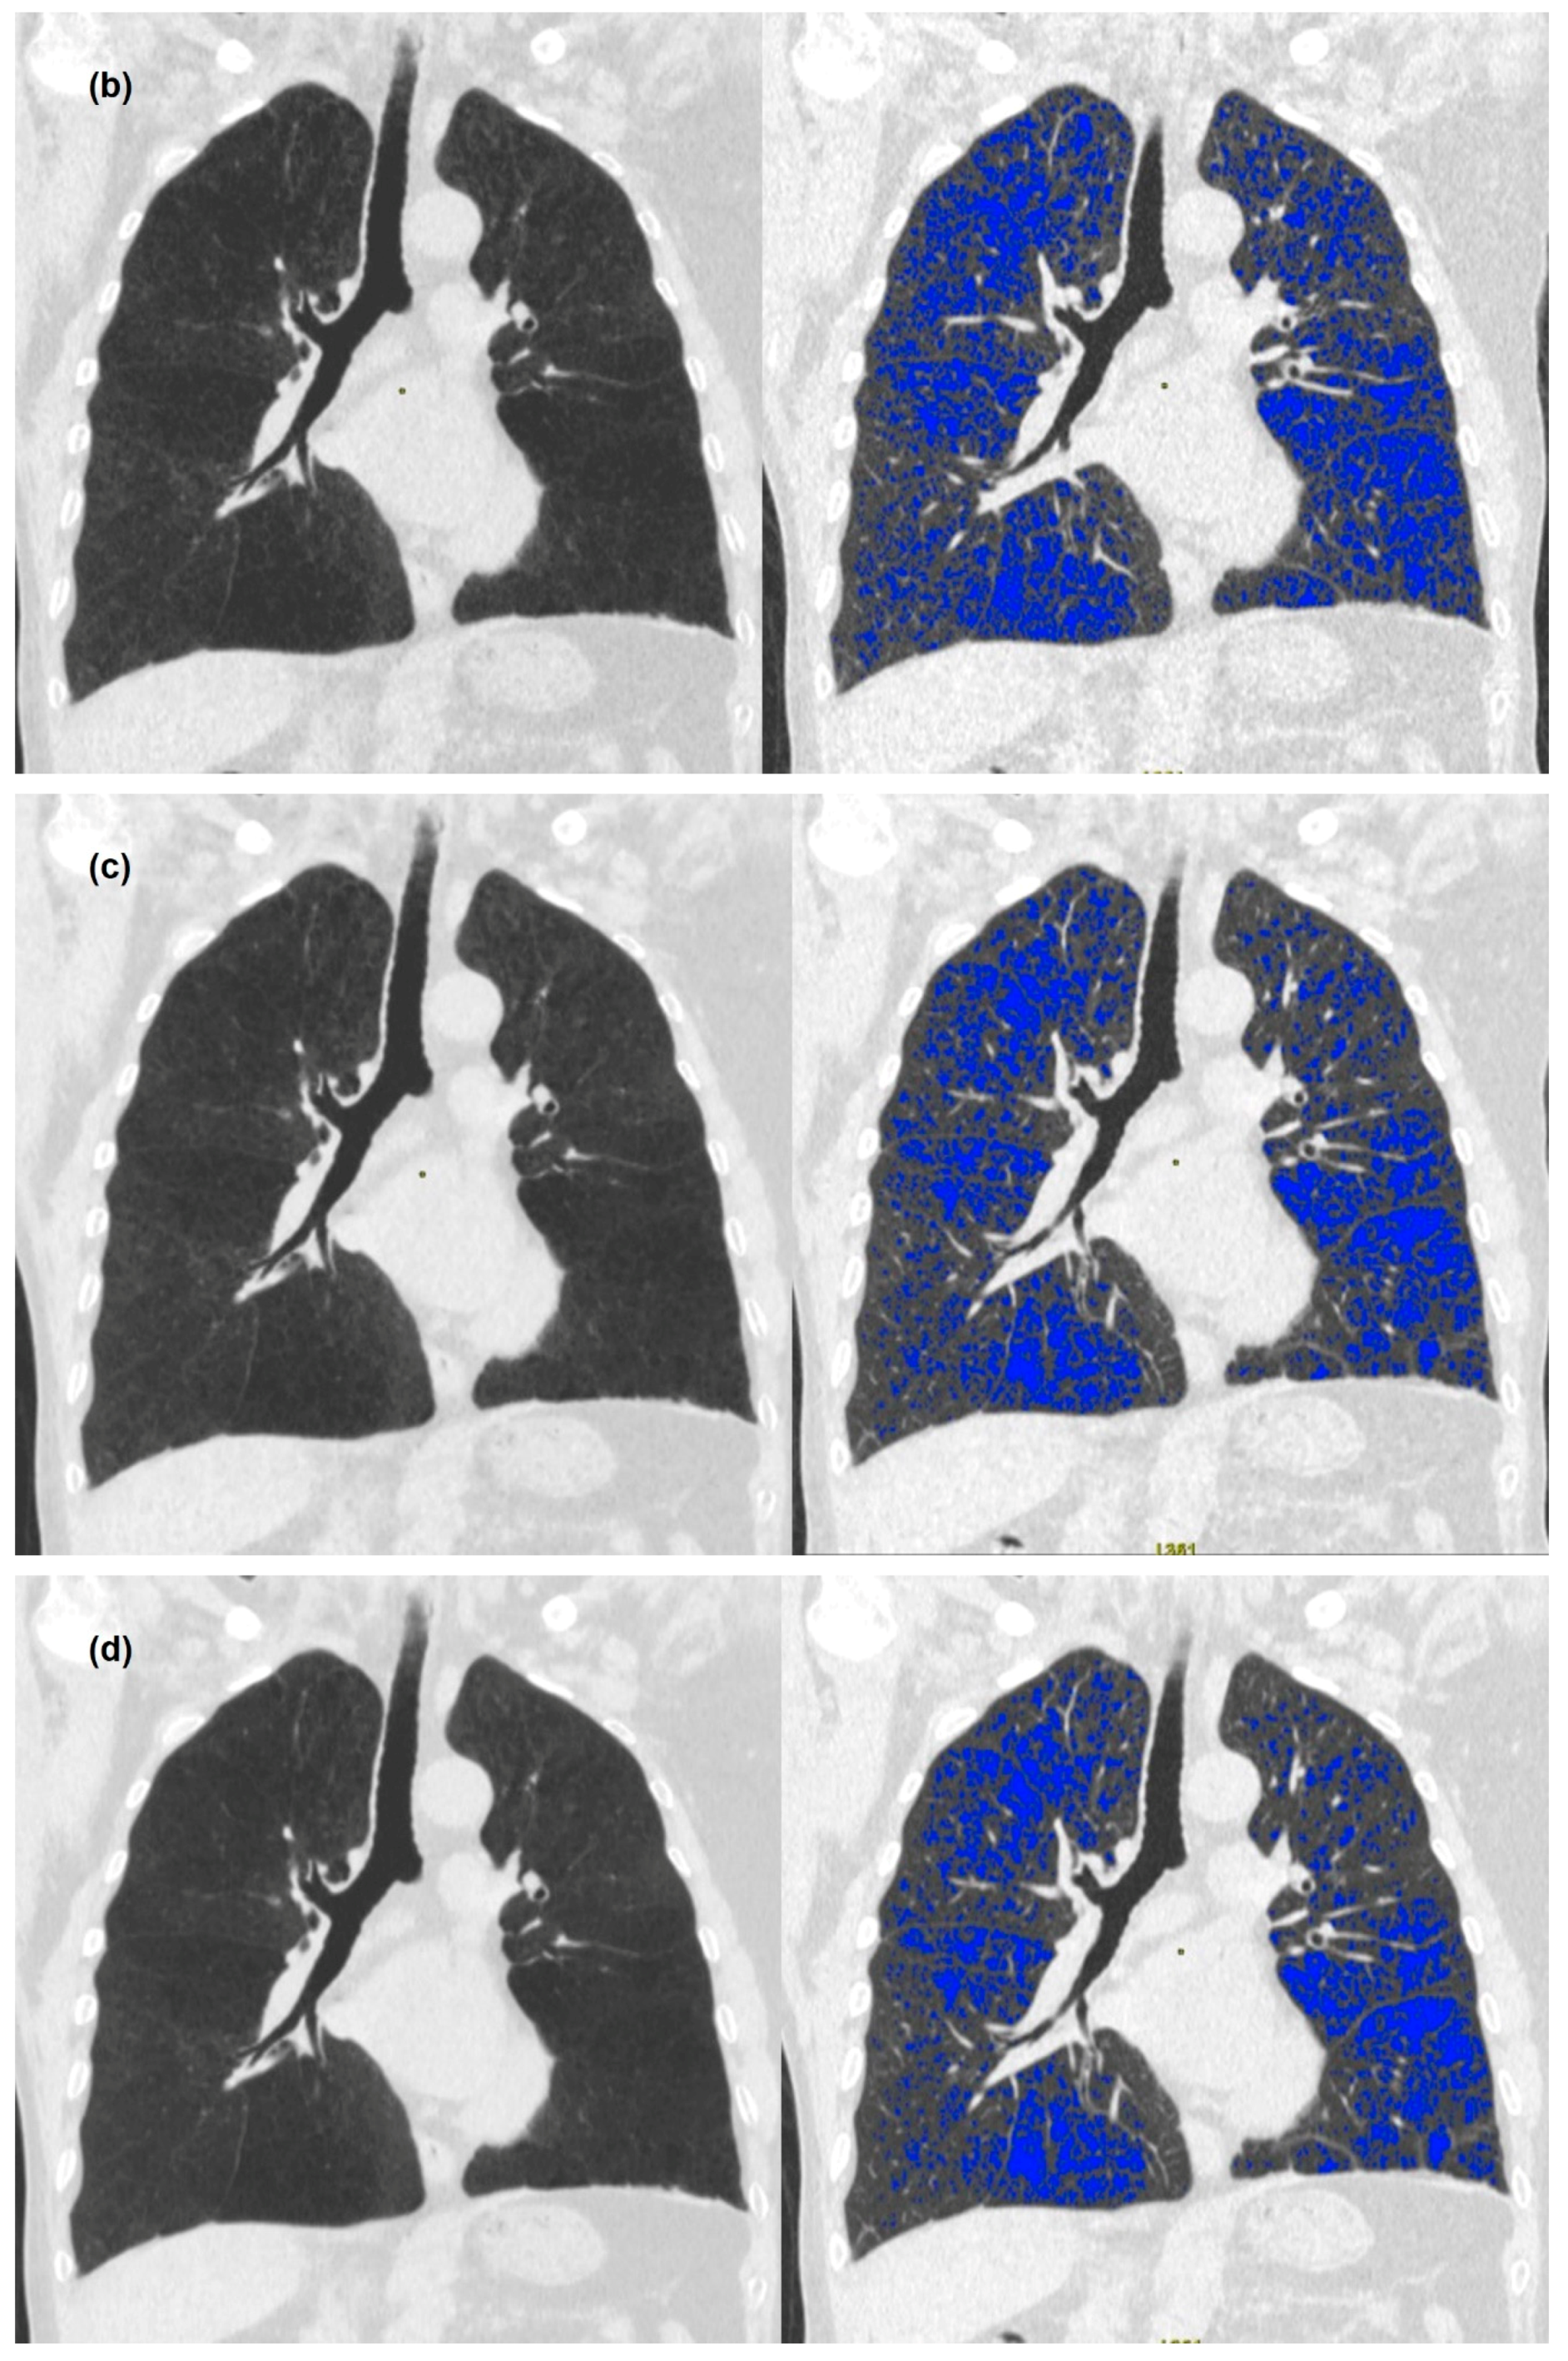

3. Results

3.2. Quantitative Measurements of Standard-Dose and Ultra-Low-Dose CT

4. Discussion